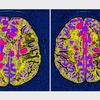

Multipla skleroza Profimedias

Multipla skleroza je bolezen, pri kateri človekov imunski sistem napade centralni živčni sistem. Prizadeti so možgani, hrbtenjača in očesni živci.